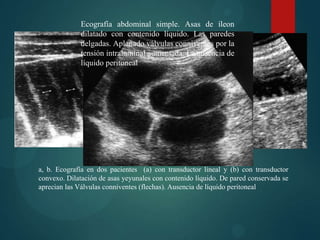

Ecografía

   Técnica: sonda convex de 3,5-5-7

Mhz. Sonda lineal de alta

frecuencia para áreas de interés,

de localización superficial,

pacientes delgados.

   Puede estar indicada : En

pacientes muy graves que no

pueden pasar a la mesa de TC

   Múltiples asas de ID dilatadas y

llenas de líquido, con

engrosamiento de la pared y

peristalsis, localización valvulas y

etiología.

Ecografía abdominal simple. Asas de íleon

dilatado con contenido líquido. Las paredes

delgadas. Aplanado válvulas conniventes por la

tensión intraluminal aumentada. La ausencia de

líquido peritoneal

a, b. Ecografía en dos pacientes (a) con transductor lineal y (b) con transductor

convexo. Dilatación de asas yeyunales con contenido líquido. De pared conservada se

aprecian las Válvulas conniventes (flechas). Ausencia de líquido peritoneal

Ecografía  Técnica: sonda convex de 3,5-5-7 Mhz. Sonda lineal de alta frecuencia para áreas de interés, de localización superficial, pacientes delgados.  Puede estar indicada : En pacientes muy graves que no pueden pasar a la mesa de TC  Múltiples asas de ID dilatadas y llenas de líquido, con engrosamiento de la pared y peristalsis, localización valvulas y etiología.

Ecografía abdominal simple.Asas de íleon dilatado con contenido líquido. Las paredes delgadas. Aplanado válvulas conniventes por la tensión intraluminal aumentada. La ausencia de líquido peritoneal a, b. Ecografía en dos pacientes (a) con transductor lineal y (b) con transductor convexo. Dilatación de asas yeyunales con contenido líquido. De pared conservada se aprecian las Válvulas conniventes (flechas). Ausencia de líquido peritoneal